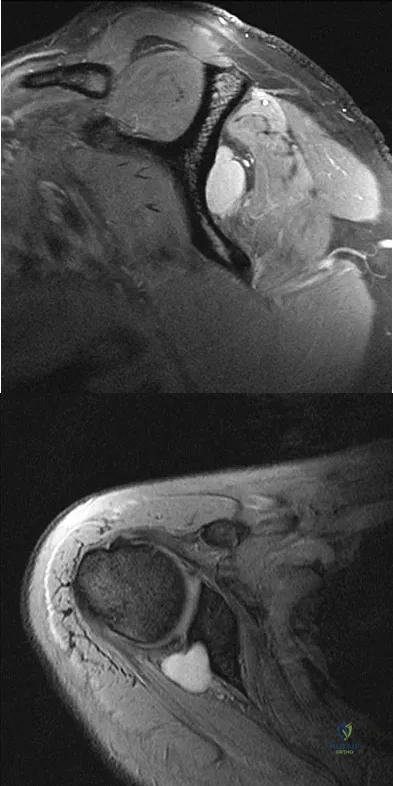

A 25-year-old tennis player has shoulder pain and weakness to external rotation. MRI scans are shown in Figures 16a and 16b. What is the most likely cause of his weakness?

Explanation